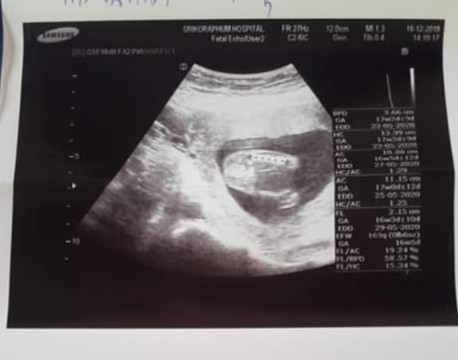

หญิงหรือชายค่ะช่วยดูหน่อยค่ะ

หมอบอกว่าชายค่ะ แต่บางคนบอกว่าซาวเป็นชายออกมาเป็นหญิงก็มี ซาวตอน17w

ถ้าชาย จะไม่ค่อยเปลี่ยนจ้า เพราะมันจะเห็นชัดกว่าผู้หญิง